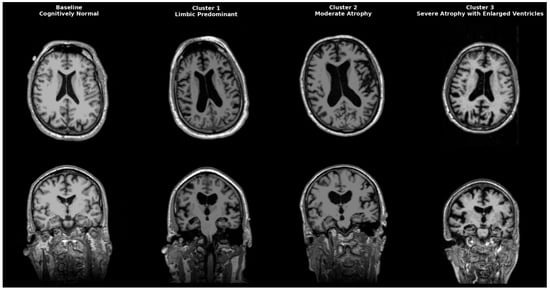

Magnetic Resonance Imaging and Cerebrospinal Fluid Biomarker Clustering Defines Biological Subtypes of Alzheimer’s Disease

by Rafail C. Christodoulou, Georgios Vamvouras, Maria Daniela Sarquis, Vasileia Petrou, Platon S. Papageorgiou, Ludwing Rivera, Celimar Morales, Gipsany Rivera, Evros Vassiliou, Elena E. Solomou and Sokratis G. Papageorgiou

Background/Objectives: Alzheimer’s disease (AD) exhibits clinical and biological variability. This study aimed to identify MRI-defined subtypes reflecting distinct biological pathways of neurodegeneration and cognitive decline. Methods: We applied principal component analysis followed by k-means clustering (k = 3) on volumetric MRI [...] Read more.

Background/Objectives: Alzheimer’s disease (AD) exhibits clinical and biological variability. This study aimed to identify MRI-defined subtypes reflecting distinct biological pathways of neurodegeneration and cognitive decline. Methods: We applied principal component analysis followed by k-means clustering (k = 3) on volumetric MRI data from 924 participants and validated clusters using cerebrospinal fluid (CSF) biomarkers (Aβ42, total tau, p-tau, CTRED, MAPres, glucose, CTWHITE). Results: Three major phenotypes emerged: (1) a tau/vascular limbic subtype with pronounced hippocampal and amygdala atrophy and elevated tau and CTRED levels; (2) a volume-preserved, low-amyloid subtype consistent with early-stage or cognitively resilient AD; and (3) a diffuse-atrophy subtype with high amyloid and tau burden and ventriculomegaly. Comparative analysis revealed progressive biological shifts from amyloid accumulation to tau aggregation and vascular compromise across these clusters. Conclusions: MRI-based clustering validated by CSF biomarkers delineates biologically meaningful AD endophenotypes. The results suggest a gradual cognitive decline driven by amyloid–tau–vascular interactions, supporting multimodal phenotyping as a practical approach for precision staging and intervention. Full article